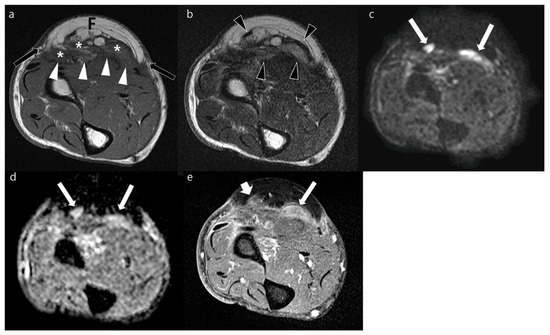

| Variables | Local Recurrences (n = 40) | Postoperative Changes (n = 36) | p Values | |

|---|---|---|---|---|

| Location on the transplanted soft tissue a | Peripheral margin | 25 | 22 | 0.907 |

| Deep margin | 11 | 12 | 0.583 | |

| Regional | 7 | 3 | 0.241 | |

| Border | Well-defined | 30 | 9 | <0.001 * |

| Ill-defined | 10 | 27 | ||

| Shape | Nodular | 39 | 20 | <0.001 * |

| Non-nodular | 1 | 16 | ||

| Size (cm) b | 2.6 ± 2.2 | 1.7 ± 1.0 | 0.020 * | |

| Sequences | Signal Intensity of MRI | Local Recurrences (n = 40) | Postoperative Changes (n = 36) | Hyperintensity vs. iso- or Hypointensity (p Value) |

| T1WI | Hyperintensity | 12 | 2 | 0.007 * |

| Isointensity | 26 | 31 | ||

| Hypointensity | 2 | 3 | ||

| T2WI | Hyperintensity | 34 | 15 | <0.001 * |

| Isointensity | 4 | 17 | ||

| Hypointensity | 2 | 4 | ||

| FS-T2WI | Hyperintensity | 38 | 27 | 0.020 * |

| Isointensity | 1 | 7 | ||

| Hypointensity | 1 | 2 | ||

| Contrast-enhanced FS-T1WI | Strong | 20 | 3 | <0.001 * |

| Moderate | 18 | 31 | ||

| Mild | 2 | 2 | ||

| DWI with high b-value | Hyperintensity | 37 | 30 | 0.294 |

| Isointensity | 1 | 4 | ||

| Hypointensity | 2 | 2 | ||

| ADC (μm2/s) a | 1297.0 ± 590.9 | 1634.6 ± 462.7 | 0.008 * | |

| Impeded water diffusion | Positive | 22 | 5 | <0.001 * |

| Negative | 18 | 31 | ||